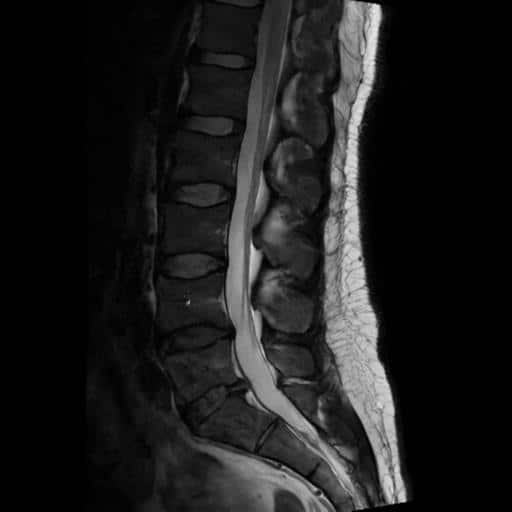

I got an MRI from a radiology clinic and confirmed that there was compression at the S1 nerve root. This at least ruled out more serious complications, but it also showed that we could really target that for recovery.

The injection was quick and easy. Just a couple of small pricks. First, the local anaesthetic, and then the injection. The radiologist looked at the imaging, and along with my symptoms, confirmed everything was consistent with an S1 nerve root inflammation. So that’s what he targeted.